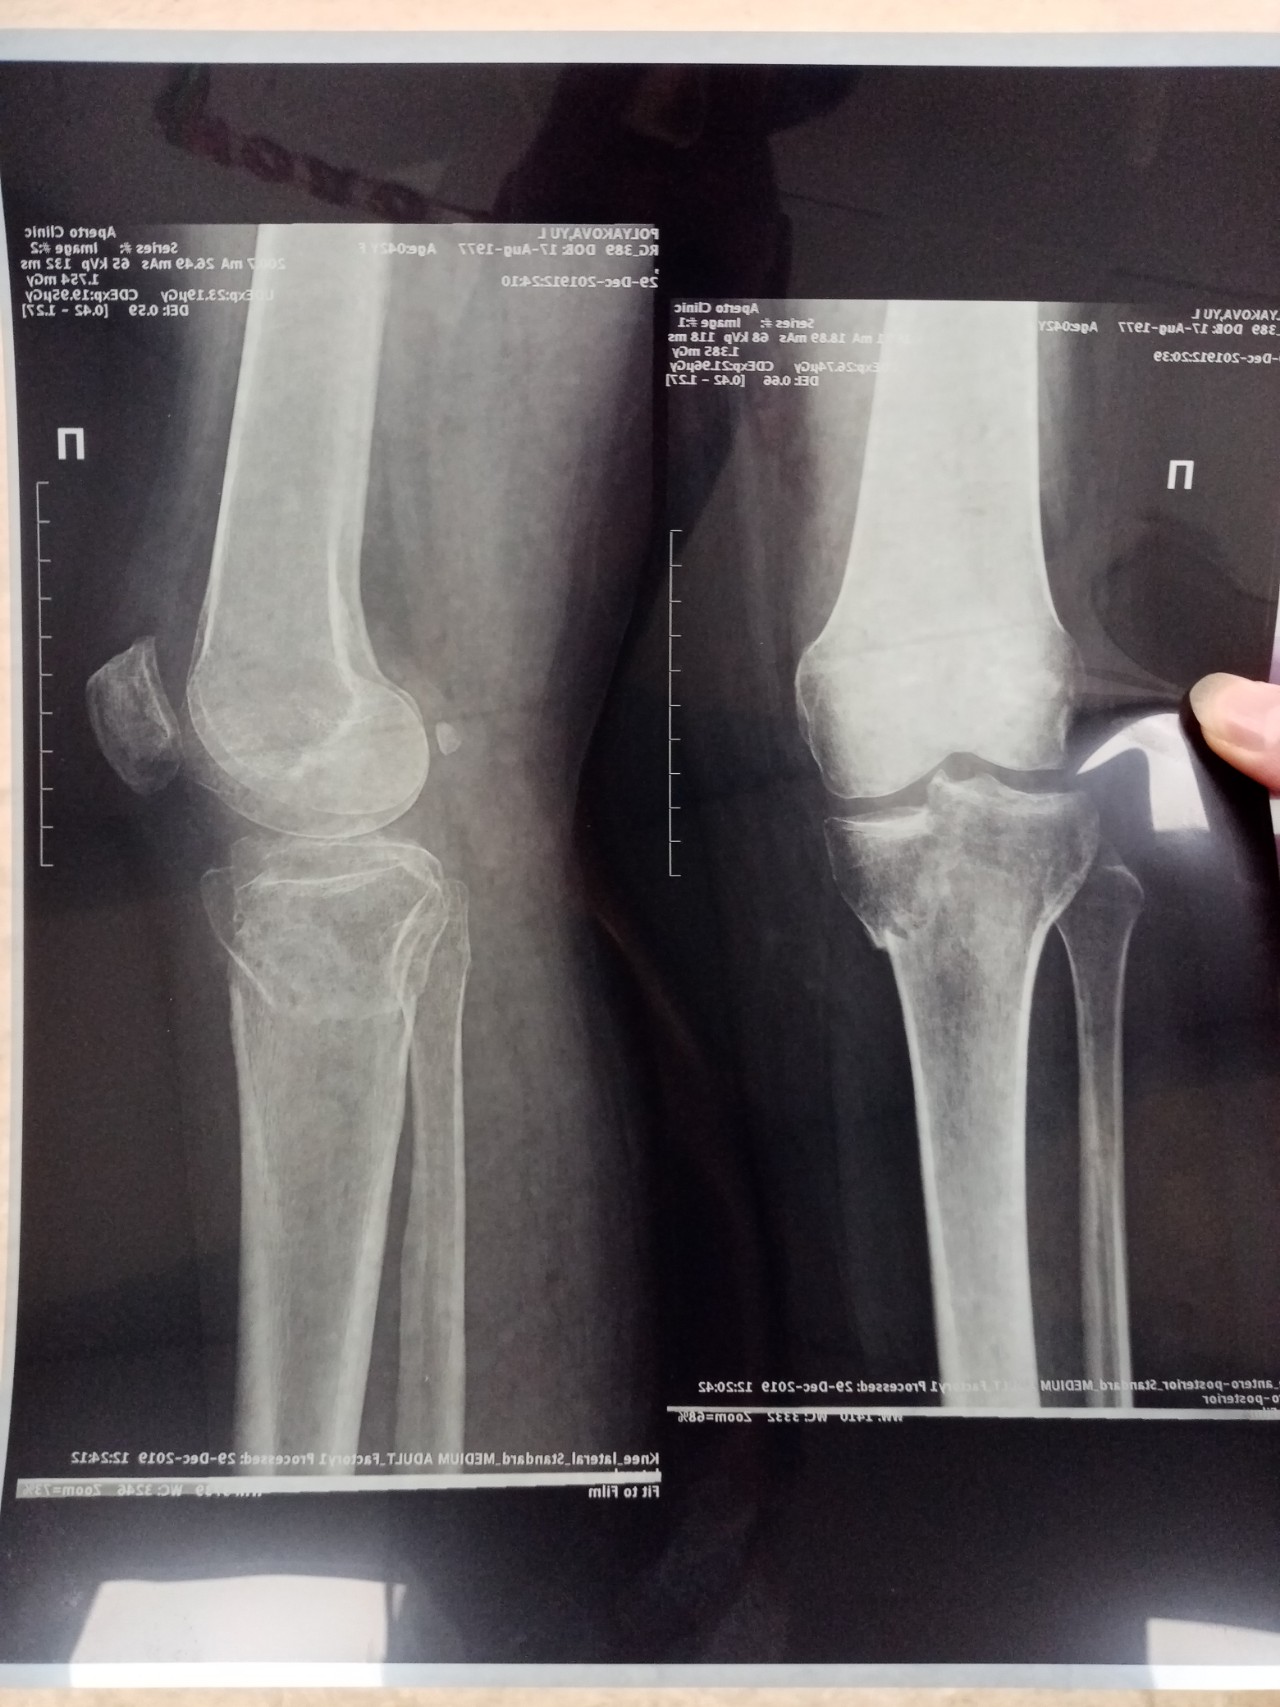

Перелом большой берцовой кости - серьезное повреждение, сопровождающееся болезненными ощущениями и нарушением функции ноги. На этой странице вы найдете много фотографий, позволяющих вам более детально изучить эту травму.

Большеберцовая кость рентген

Здесь представлены медицинские изображения переломов большой берцовой кости, сделанные врачами в процессе диагностики и лечения. Вы сможете увидеть, как выглядит этот тип травмы на рентгеновских снимках и других медицинских изображениях.